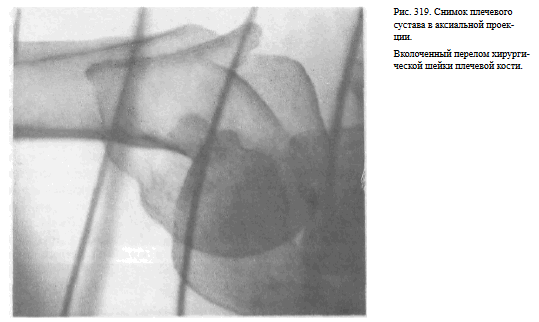

СНИМОК ПЛЕЧЕВОГО СУСТАВА В АКСИАЛЬНОЙ ПРОЕКЦИИ

Назначение снимка. Снимок предназначен для отображения плечевого сустава в плоскости, перпендикулярной к фронтальной, в которой производятся снимки в прямой задней проекции. Снимок в аксиальной проекции дает возможность определить направление смещения головки плечевой кости при вывихе в плечевом суставе, а также характер смещения отломков при переломах проксимального отдела плечевой кости.

Информативности снимка. На снимке видны головка плечевой кости, края суставной впадины лопатки, плечевой и клювовидный отростки.

Краеобразующими являются малый бугорок плечевой кости, передняя поверхность диафиза плеча по верхнему контуру и задняя поверхность диафиза плеча по нижнему контуру (рис.318, 319).